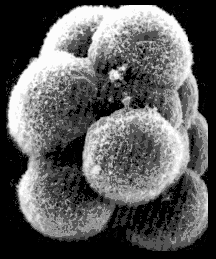

The morula

After the zygote has gone through four cleavages three days after fertilization we call it a morula.

The morula is located near the ostium of the tuba uterina